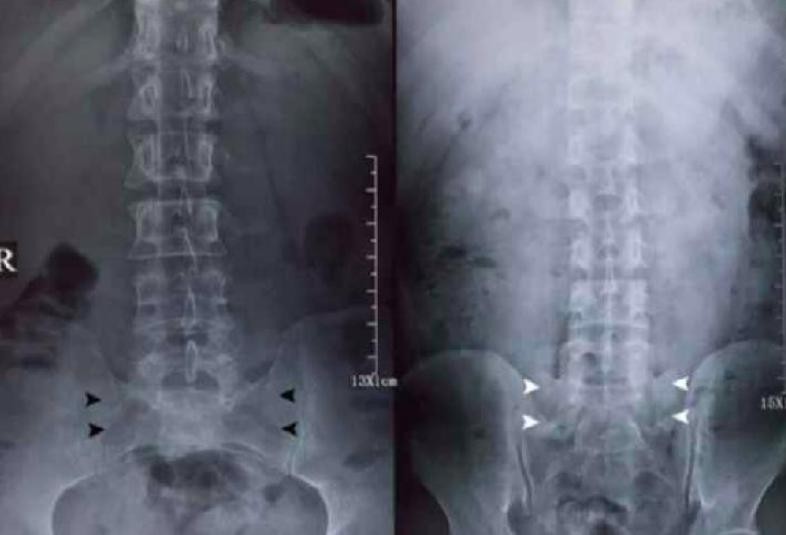

为了尽快明确病因,于娟主动要求做核磁共振检查,检查结果让医生也为之一惊:她的脊椎骨架上弥漫着不明的阴影,医生怀疑她可能患上了血液病,或者是某种实体瘤的转移。

然而,经过一系列更详细的检查,最终确诊为乳腺癌,且已经发展到第四期,这一消息如同五雷轰顶,让她的世界瞬间崩塌。